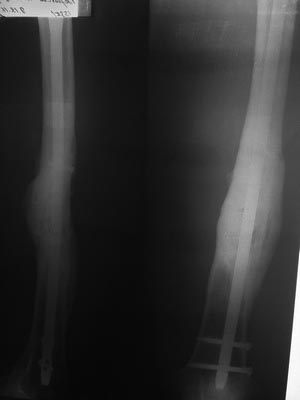

[Ortho] Консолидирующийся многооскольчатый перелом бедренной кости после БИОС. Какую тактику бы вы посоветовали?

есть отдаленный результат. в феврале сделана костная аутопластика

(расщеп малоберцевой кости + крыло подвздошной кости) + аллопластика +

PRF. От динамизации убежал. На сейчас: жалоб нет, полная нагрузка,

спорт. Травма 26.09.2015, закрытая репозиция, БИОС PFNA Long 28.09.2015,

февраль 2016 - костная пластика. Ссылка на медиаресурс